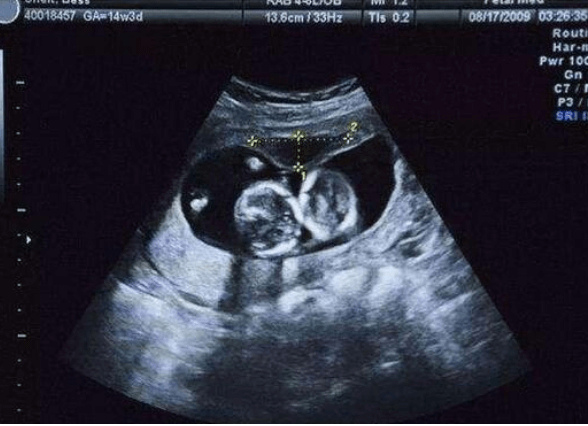

30歲,確診為多囊,備孕一年多無果,走上試管之路。選擇醫生也是糾結了好久,最終還是選擇了上海九院的傅醫生,此後的關鍵步驟都是傅醫生親自上陣。經過促排取卵後,我取出了17個,受精15個,凍胚8個,囊胚2個,最後有了10個胚胎。然後移植著床了三個胚胎,醫生建議我減胎一個,成功懷上了兩個寶寶。整個過程還是比較艱辛的,但是我覺得這一切都是值得的,現在就慢慢等待寶寶出生了。匡醫生or傅醫生選擇醫生也是糾結了...